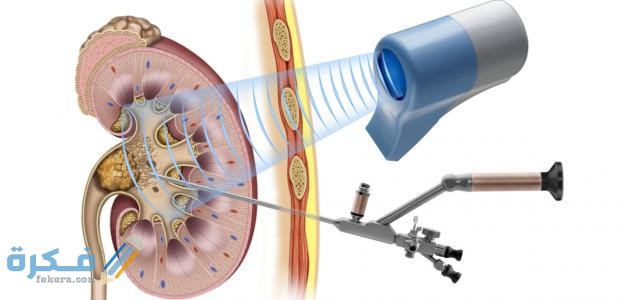

- في حالة تعثر نزول الحصوات بشكل تلقائي عن طريق الادوية يتطلب الأمر تدخل جراحي من خلال امرار جهاز من المجري البولي وصولا للمثانة والكلى وشفط الحصوات .